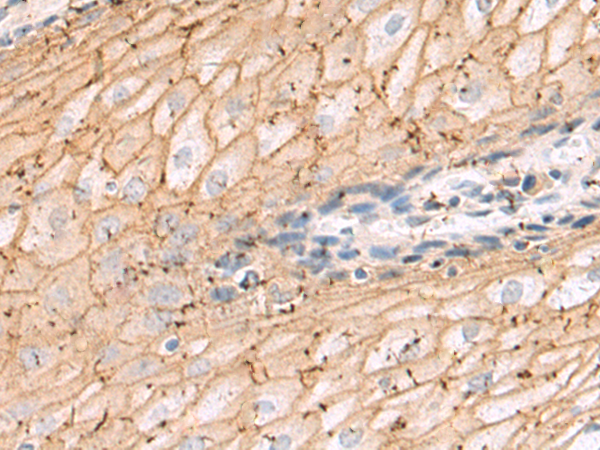

分类: 科研抗体货号: P10621别名: POR1应用: IHC反应种属: Human, Mouse, Rat